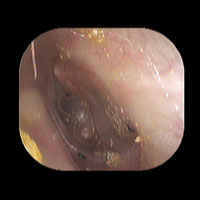

左急性中耳炎(軽症)

鼓膜がやや赤くなっています。鼓膜の奥に膿が透けて見えています。鼓膜の腫れはありません。抗生剤の内服で鼓膜切開を行わずに7日目で治りました。

初診日